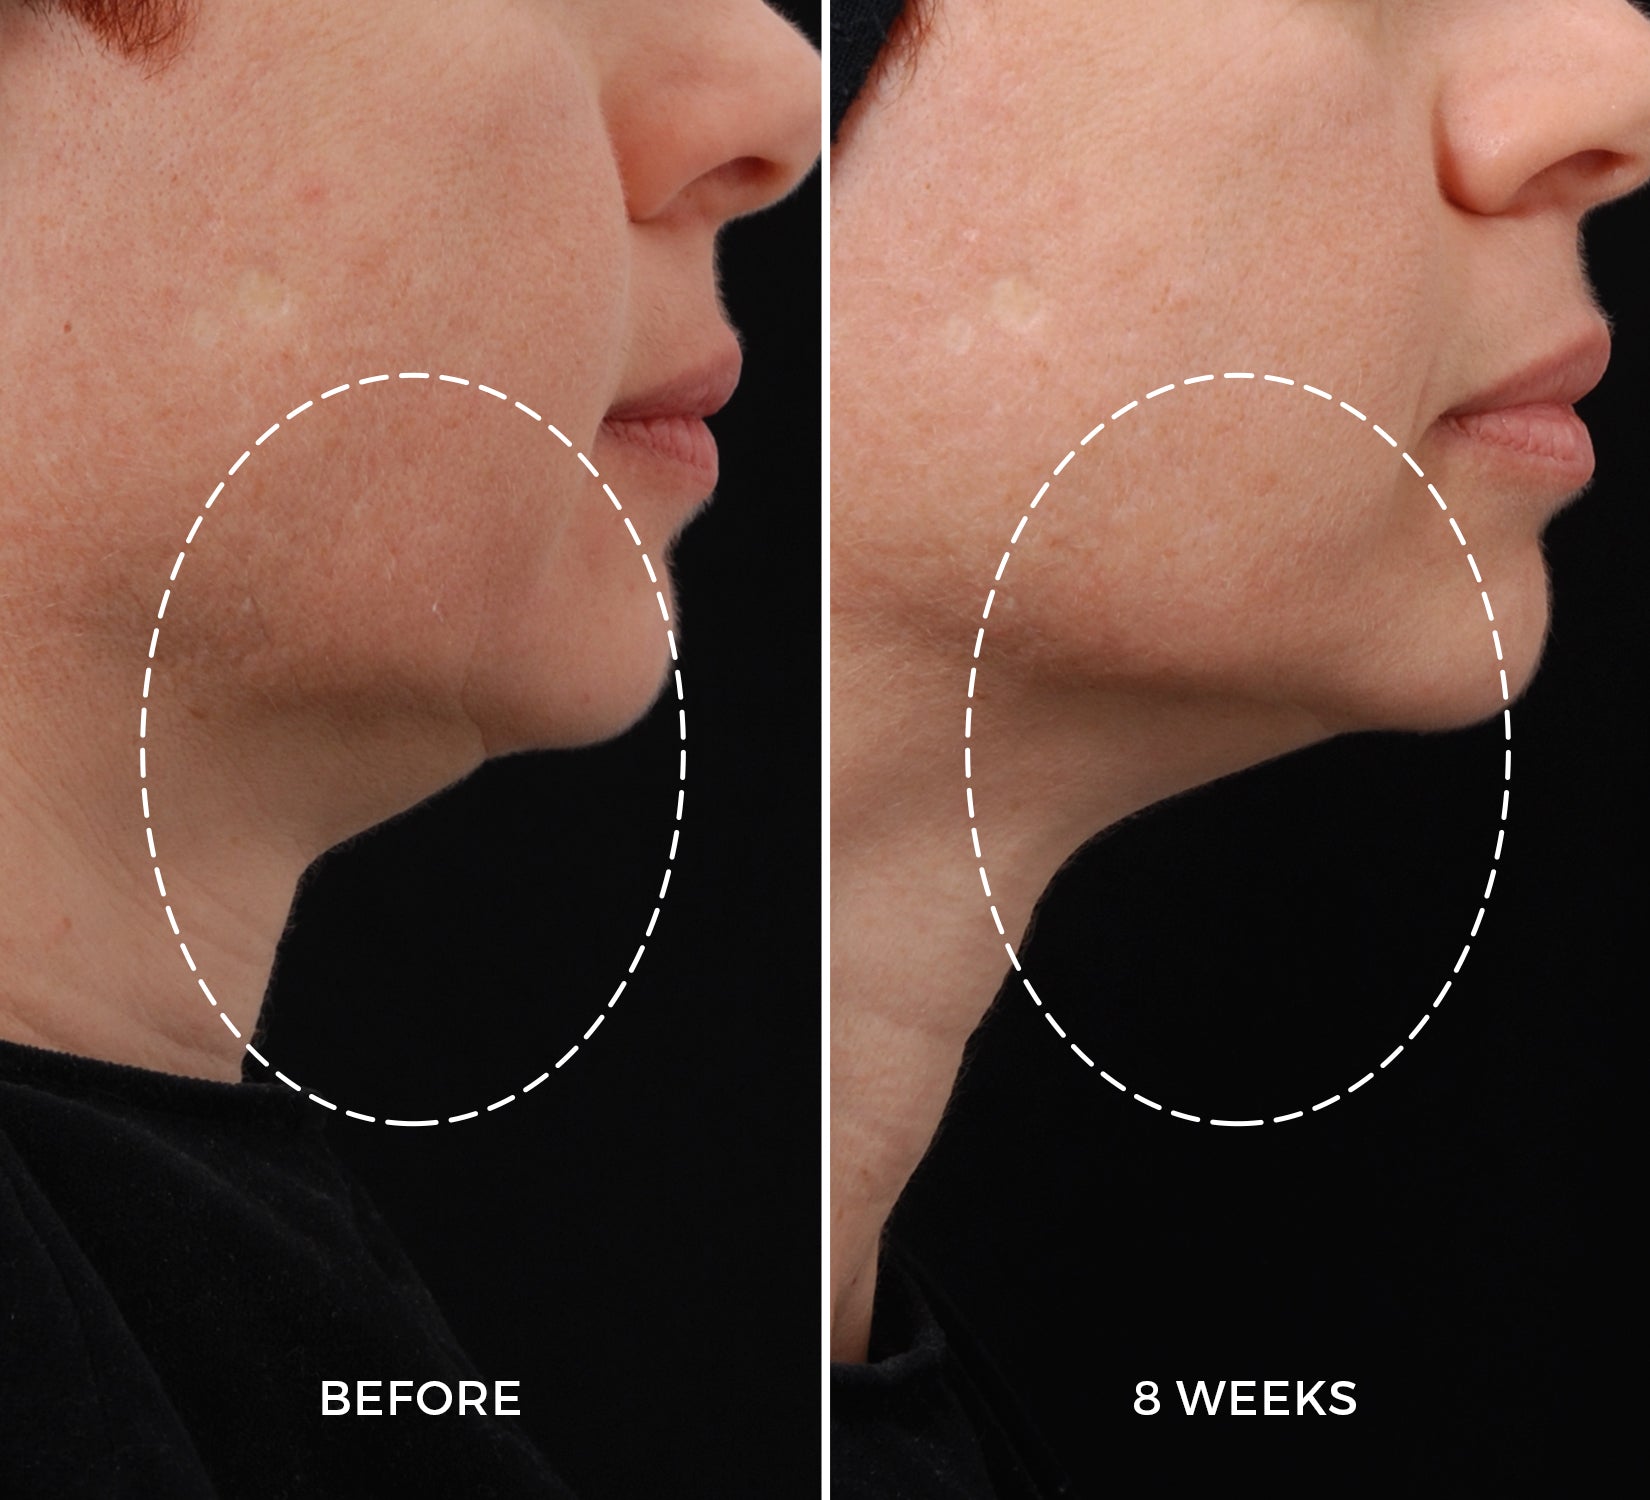

Jawline

Jawline

The benefits of the NEWA device and NEWA Lift Gel on the skin’s collagen production were clinically tested on participants of various skin types aged 37 to 65. Over a period of three months, individuals who took part in the study used the NEWA combination 3 times a week for the first 4 weeks and twice a week for the remaining 8 weeks. The results were assessed by dermatologists.²

of participants showed improvement in overall wrinkle appearance.

of participants showed improvement in skin firmness.

of participants showed an increase in skin collagen content